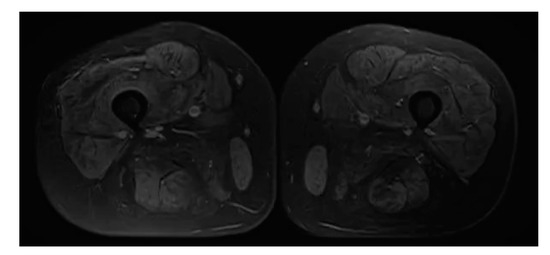

Sarcotubular Myopathy Due to Novel TRIM32 Mutation in Association with Multiple Sclerosis

Azerbaijani 28-year-old female showed weakness (MRC (Medical Research Council Scale for Muscle Strength) grade 4 in the proximal part of the upper and MRC grade 2–3 in the lower extremities), difficulty in stair lifting, positive symptom of Hoover’s rising, «waddling gait», decline deep [...] Read more.

Azerbaijani 28-year-old female showed weakness (MRC (Medical Research Council Scale for Muscle Strength) grade 4 in the proximal part of the upper and MRC grade 2–3 in the lower extremities), difficulty in stair lifting, positive symptom of Hoover’s rising, «waddling gait», decline deep reflexes symmetrical, lack of surface reflexes, positive Babinsky’s reflex on the right, urinary incontinence during sneezing, prolonged walking and exercise from puberty. Additional methods made it possible to identify minor violations of conduction of the left ventricle, electromyography signs of primary muscular disease with predominant involvement of the proximal muscles of the lower extremities, elevation of serum creatine kinase (746.81 U/l), active foci of demyelination in the left frontal lobe, intrathecal synthesis of oligoclonal IgG bands (type 2) in cerebrospinal fluid, atrophy and fatty degeneration of all muscles of the shins, homozygous Variant of Uncertain Significance (VUS) c.1855C > T (p.Pro619Ser) in TRIM32 gene and heterozygous VUS c.2300C > G (p.Thr767Arg) in KIF5A, c.2840G > A (p.Arg947Lys) in MYH2, c.1502G > C (p.Gly501Ala) in POMT1 genes. Comparison of the phenotypes of the mutations that have been identified with the clinical picture of the patient suggests that VUS c.1855C > T (p.Pro619Ser) in the TRIM32 gene can be pathological. Summarizing, it can be argued that the cause of the identified disorders is a homozygous variant c.1855C > T (p.Pro619Ser) in TRIM32 gene that causes LGMDR8 in a patient with MS. Full article

Figure 1